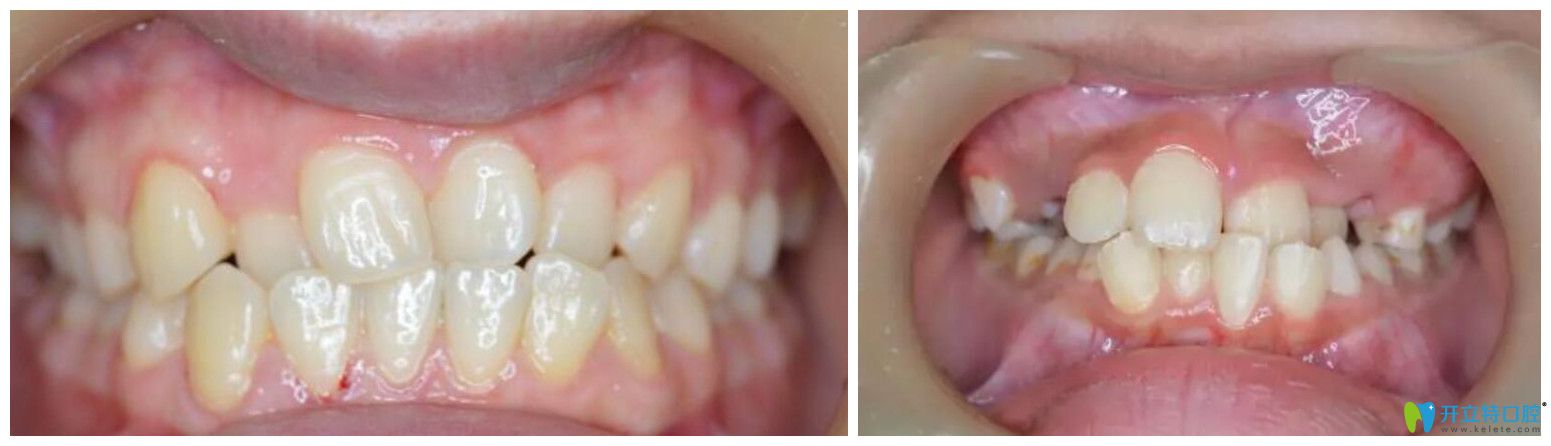

2、個(gè)別牙反合

通常的表現(xiàn)是個(gè)別門牙或兩顆牙反合。會影響到孩子上面部的正常發(fā)育,可能導(dǎo)致孩子的上唇部凹陷。而且,其潛在的危害是,較有可能導(dǎo)致兒童成長到3040歲時(shí)出現(xiàn)顳下頜關(guān)節(jié)紊亂病。

個(gè)別牙反合